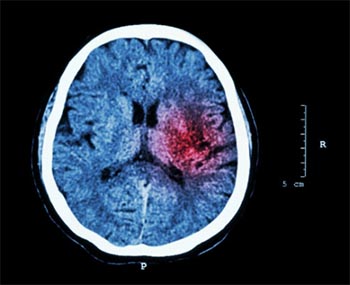

Si se han presentado algunos síntomas como los que se han comentado anteriormente, se deberá acudir inmediatamente al médico para que realice las pruebas necesarias para otorgar un diagnóstico específico. Para poder llevar a cabo esta evaluación y determinar si el derrame cerebral es hemorrágico o isquémico, para iniciar uno u otro tratamiento, los doctores suelen realizar las siguientes pruebas médicas:

- TAC: mediante los rayos X y las fotografías del interior del cuerpo se determinará si se ha sufrido un accidente y si éste ha sido provocado por un coágulo o por un derrame de sangrado en el cerebro.

- RMN: mediante los pulsos de radiofrecuencia y los campos magnéticos se obtienen imágenes de los órganos que permite analizar el estado de los vasos sanguíneos cerebrales y evaluar daños.